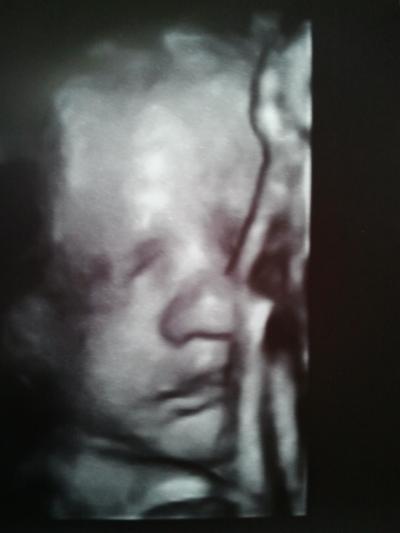

Hallo Mädels, hatte heute mein 3. Screening und es ist alles in Ordnung. Bubi liegt weiterhin in SL und ist schon ca. 45 cm groß. Hat aber "nur" 1800- 1.900 Gramm. Ich weiß, man soll nicht viel auf diese Werte geben, aber ist das für diese Größe nicht zu leicht ? Kopfumfang (29,9), Bauchumfang etc. alles normal. Mir wurde ja schon in der 12. SSW gesagt, dass unser Kleiner wahrscheinlich eher kommt (ein paar Tage) , und ich mich wohl im Zyklus verrechnet hätte. Tja, ich hatte ja gar keine Möglichkeit meinen Zyklus auszurechnen , denn ich bin im 2 ÜZ nach der Pille schon schwanger geworden. Ich hoffe wirklich, dass die Ärzte Recht behalten, ich kann es nämlich auch noch kaum erwarten und möchte endlich kuscheln. ;) Die Hitze macht mich zu schaffen, hab Wasser in den Beinen und mal wieder Sodbrennen :( Die letzten Wochen schaff ich aber auch noch. Ab Donnerstag in der 33. SSW......... Häng Euch noch ein 4D Foto mit dran....leider hat er mal wieder das halbe Gesichtchen mit seinem Arm verdeckt.....Bin trotzdem voll verliebt Grüßle Mandy

Bild zu 3. Screening ..... - Forum für August - Mamis